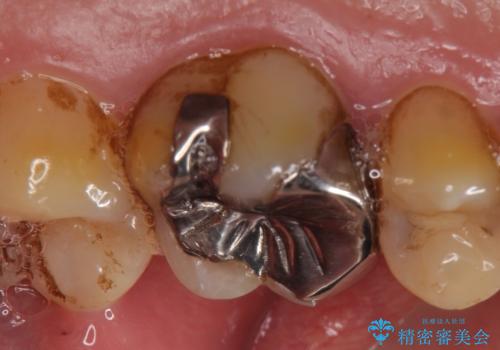

- ものを咬むと左上の奥歯が痛むので診て欲しいといらっしゃった方の症例です。

診査の結果、左上6が失活(歯の神経が死んでいる状態)しており根尖病変を認めたため、根管治療を行いました。

根尖病変の縮小及び症状の消失を確認後、オールセラミッククラウンによる補綴を行いました。